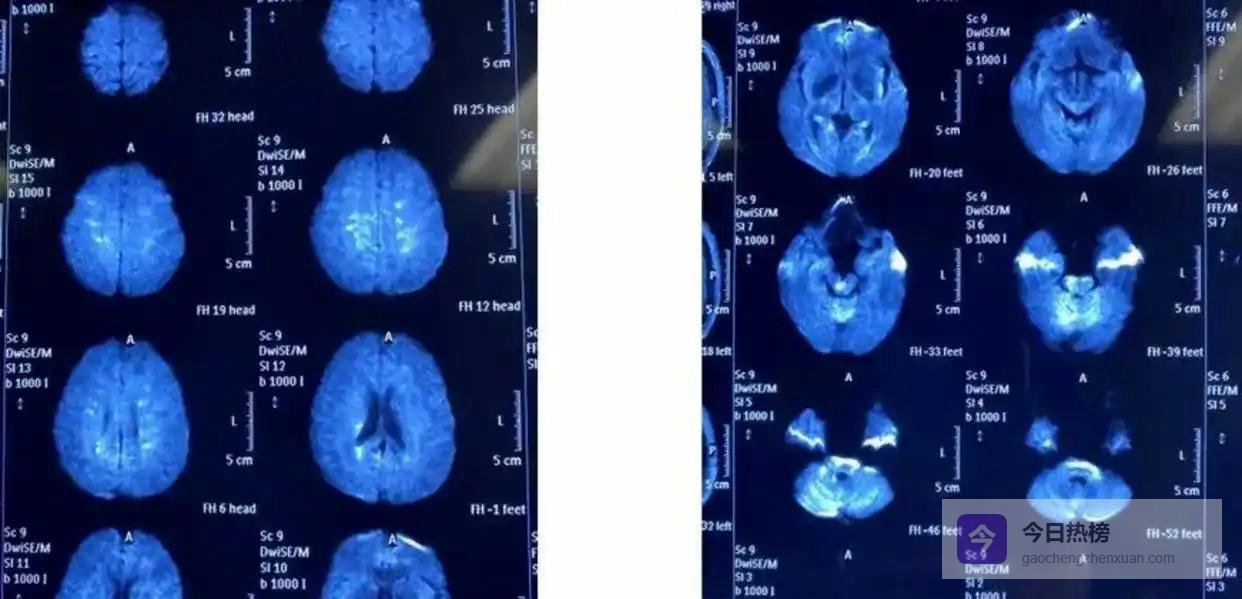

男人开车时遭遇闯红灯的大货车,当场昏迷。全身多处骨折,在重症监护室抢救两天才捡回一条命。醒来后,妻子告诉他一个残酷的事实:给所有亲戚都群发通知了,没人搭理。